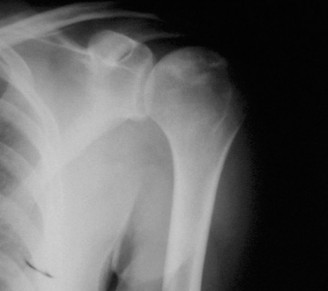

It should be noted that reverse total shoulder arthroplasty is also the procedure of choice in patients with cuff-tear arthropathy (aka rotator cuff arthropathy). Characteristics of cuff-tear arthropathy include superior migration of the humerus due to a massive rotator cuff tear, glenohumeral joint destruction, subchondral osteoporosis, and humeral head collapse (see Fig. 2–17). A reverse total shoulder

Figure 2–17_X-rays of a patient showing evidence of cuff tear arthropathy. The humerus is migrated superiorly, the glenohumeral joint is destroyed, there is subchondral osteoporosis, and the humeral head is collapsed. (From Ecklund KJ, Lee TQ, Tibone J, Gupta R. Rotator cuff tear arthropathy. _J Am Acad Orthop Surg. 2007;15(6):340–349.)